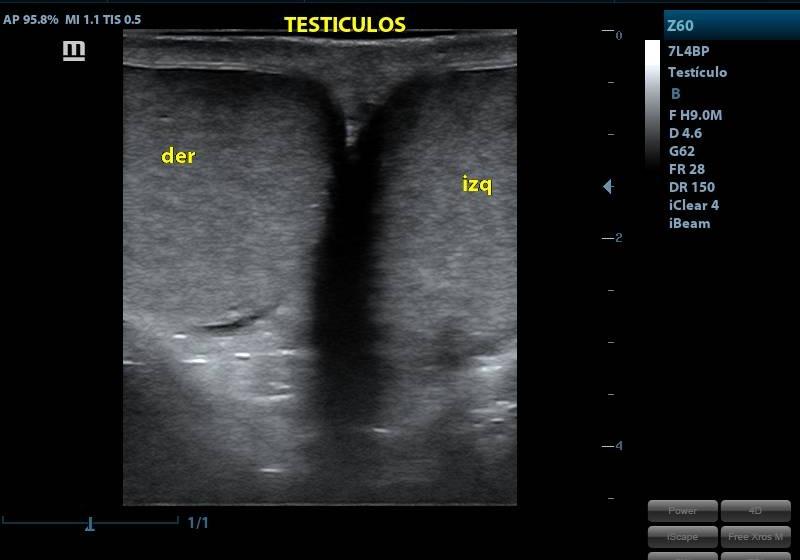

ECOGRAFIA TESTICULAR

SERVICIOECOGRAFIA

PRESENTACIÓNECOGRAFIA

CONDICIÓNPRESENTARSE CON ROPA LIGERA

TIEMPO10 MINUTOS

TIPO RESULTADOSIMAGENES ECOGRAFICAS

ESPECIFICACIONESUTILIZA ONDAS SONORAS REFLEJADAS PARA PRODUCIR UNA IMAGEN DE LOS TESTÍCULOS Y EL ESCROTO. ESTA PRUEBA PUEDE MOSTRAR EL TUBO LARGO Y FUERTEMENTE ENROLLADO QUE ESTÁ DETRÁS DE CADA TESTÍCULO Y QUE RECOLECTA LOS ESPERMATOZOIDES (EPIDÍDIMO). TAMBIÉN PUEDE MOSTRAR EL TUBO (CONDUCTO DEFERENTE) QUE CONECTA LOS TESTÍCULOS CON LA PRÓSTATA. LA ECOGRAFÍA NO USA RADIOGRAFÍAS NI OTRO TIPO DE RADIACIÓN.